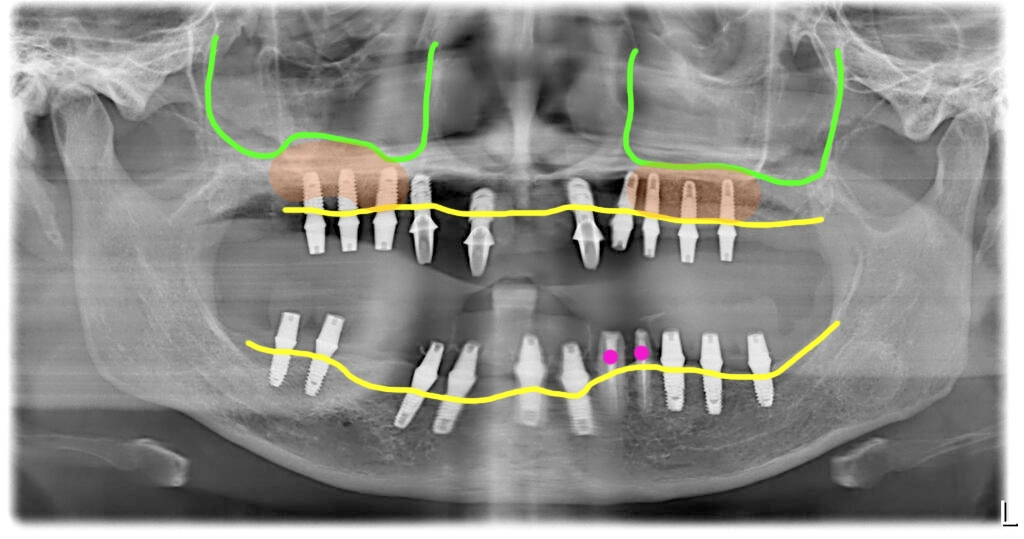

위턱에는 제일 뒤에 어금니 한 개만 남아있는 무치악 상태였습니다. 엑스레이에서 보시듯이 상악동이 앞뒤로 아주 길면서 크고 가용골(이용할 수 있는 뼈)이 전혀 없어서 뼈이식과 함께 임플란트를 식립해서 고정을 얻기가 어려운 상태였습니다.

첫번째 수술입니다. 상악에 한개 남은 치아는 제거하고 대량의 뼈이식을 진행했습니다. 고정을 얻을 만한 뼈가 없어서 임플란트 식립은 뼈이식 후 6개월 차에 진행하기로 했습니다.

그래서 위쪽은 즉시하중을 적용하지 못하고 미리 만들어 둔 임시틀니를 착용했습니다.